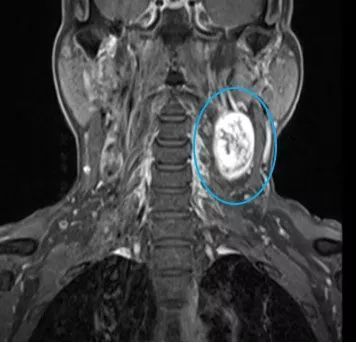

张先生和赵先生住院以后都做了颈部的磁共振检查,检查结果显示张先生的肿块长在了下颌角的边上,肿块还包绕着颈部的大血管。而赵先生的肿块是从臂丛神经上长出来的。

张先生颈部磁共振 医院供图